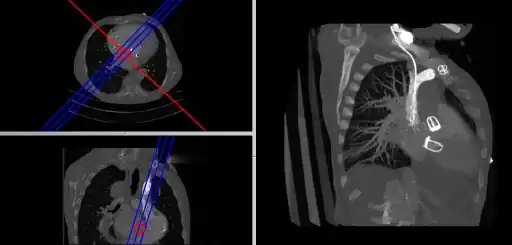

- Coronal and sagittal reconstructions are referred to as Orthogonal MPRs because the perspectives generated are from planes of image data which are at right angles to each other. Composite MPR displays can be generated so that linked cursors or crosshairs can be used to locate a point of interest from all three perspectives, as illustrated in these images:

![]() |

- This form of image presentation is sometimes referred to as a TCS display – implying the viewing of Transaxial, Coronal and Sagittal slices. It can be combined with the slice projection methods we discussed earlier, as illustrated in the two sets of images below, where the blue lines highlight the limits of the coronal projections:

- Here the plane can be defined in, say, the axial images (red line, top left) and a maximum intensity projection (the limits used are highlighted by the blue lines), for example, can be displayed for the reconstructed plane (right). This technique is useful when attempting to generate perspectives in cases where the visualization of three-dimensional structures is complicated by overlapping anatomical detail.